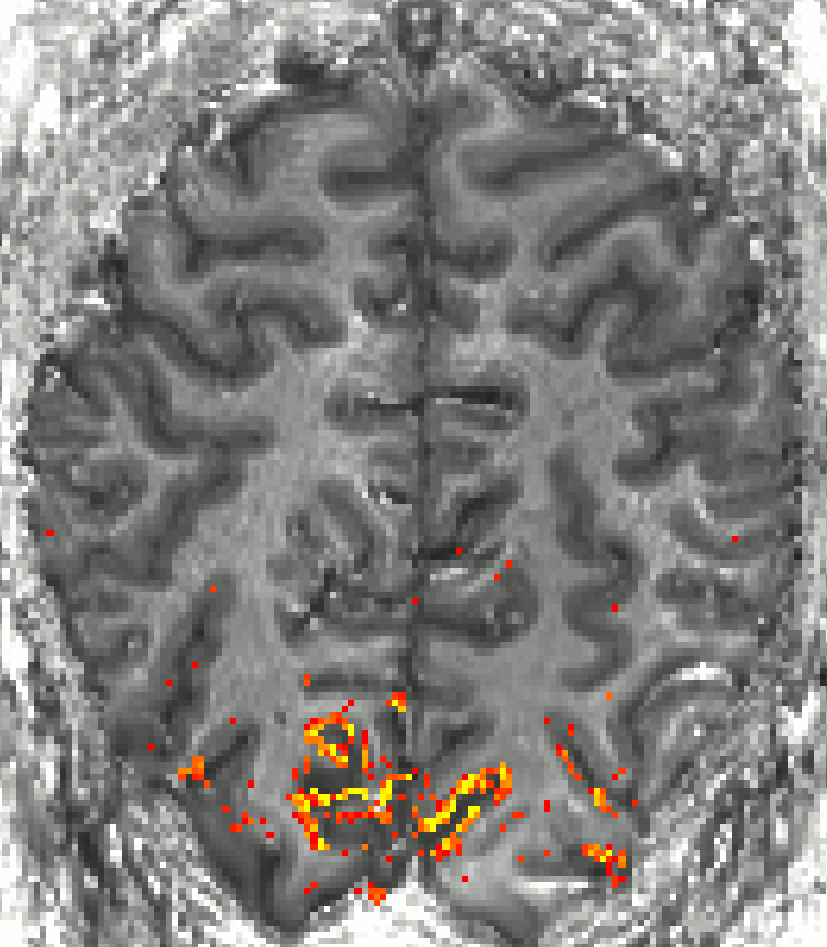

image125.gif

Activation maps for BOLD and VASO. At about 0.8 mm resolution, one starts to see that VASO is less sensitive to large draining veins.

With respect to high-resolution VASO application, visual cortex is very unique. I found it to be a challenging area. However, because of its high demand, I have been working on is with multiple collaborators. The most important pitfalls of SS-SI VASO in visual cortex that I came across in these collaborations are discussed below.